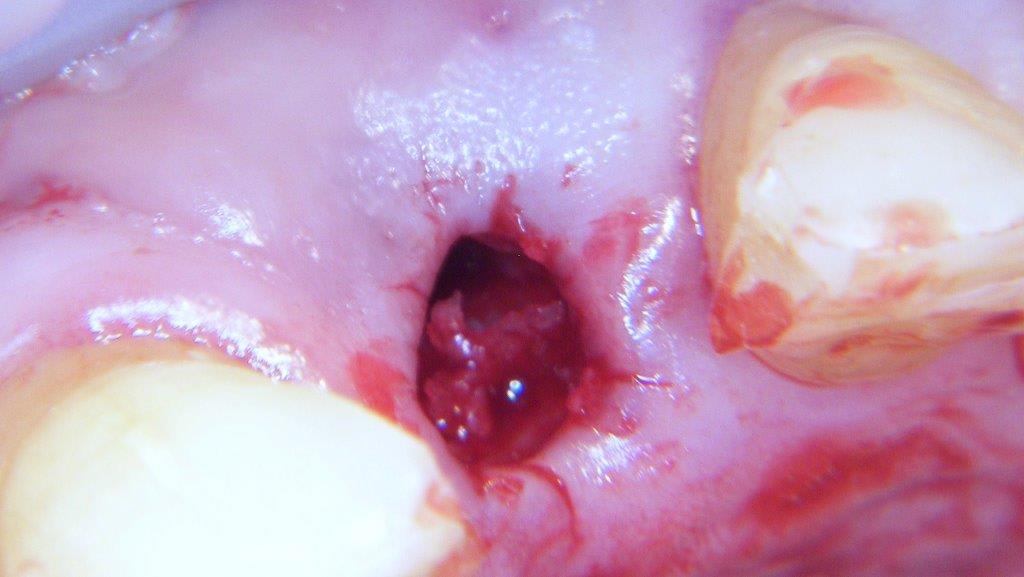

pour ceux que ça intéressent, une petite utilisation d'expansion de la paroi palatine, sur une avulsion d’incisive(racine fendue). toutes mes excuses pour la mauvaise qualité des photos.

voilà prothèse moyenne mais aucun souci